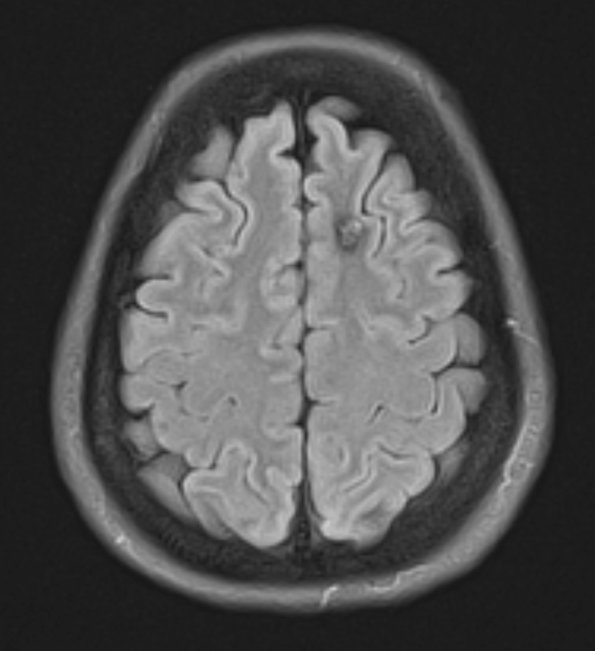

Case 30 History ---- The patient is a 38yo female with a recent seizure secondary to left frontal cavernous malformation. Brain MRI showed a 1.0 cm left frontal cavernoma with associated developmental venous anomaly. Operative procedure: left craniotomy for resection of cavernous malformation with stealth. ---- 30A1-4 MRI Studies ---- 30A1 The lesion as seen in a FLAIR scan.